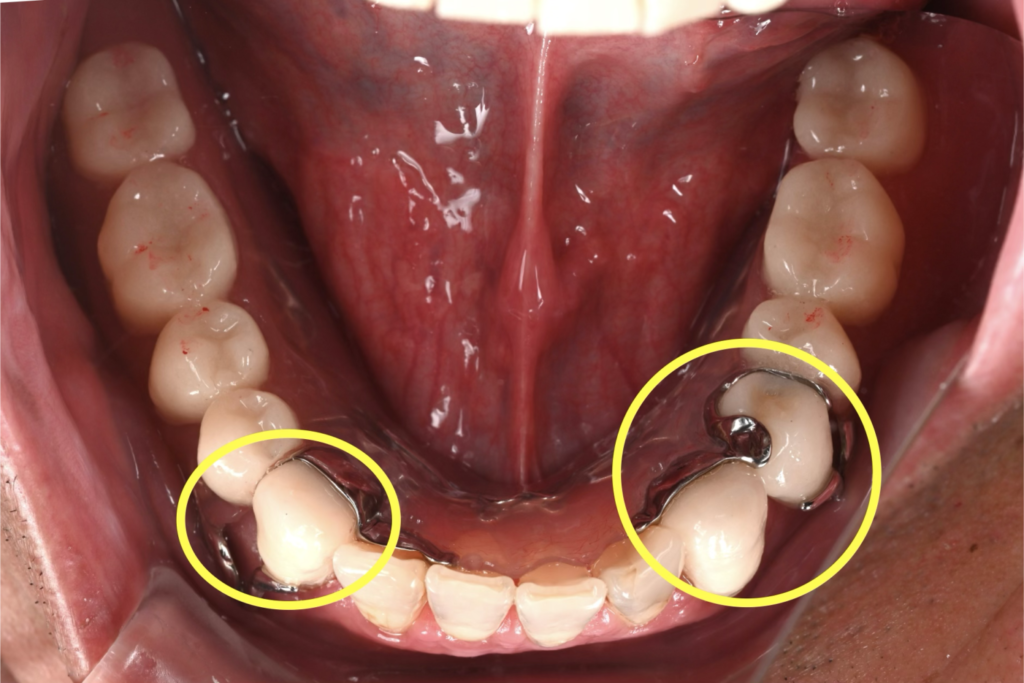

主人の場合、下顎は部分義歯タイプにする事になったので仮義歯を入れる際に、バネをかける歯に特殊な加工をしたサベイドクラウンという補綴物(被せ物)を作成しました。

入れ歯(部分床義歯)のバネ(クラスプ)が装着される歯(鉤歯)に施される、入れ歯の維持・安定を助ける特別な被せ物(クラウン)のことです。設計段階から、バネがかかる歯に対して、適切な掘り込みや面を事前に形成しておくことで、入れ歯がしっかり機能し、快適に装着できるようになります。

義歯のバネを掛ける歯だけに施す被せ物で、数本にこの処置をするだけで義歯の安定はもちろん、その歯の寿命も変わります。